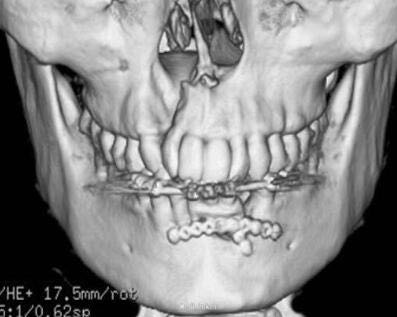

下颌骨前部牙槽突骨折,下颌骨骨折 处理:托槽固定下颌牙槽突骨折,坚固固定内固定固定下颌骨骨折

术后一个月拆除托槽,CT提示下颌骨骨折愈合中